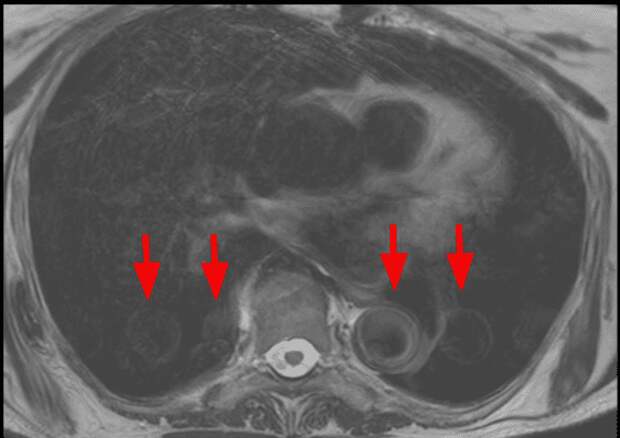

- Как выглядят: Размытые, сдвоенные контуры, "призраки" (ghosting), которые повторяются по фазовому направлению.

- Как выглядят: Локальные "вспышки" яркого сигнала, полосы и черные "дыры" с полной потерей сигнала, геометрические искажения контуров органов.